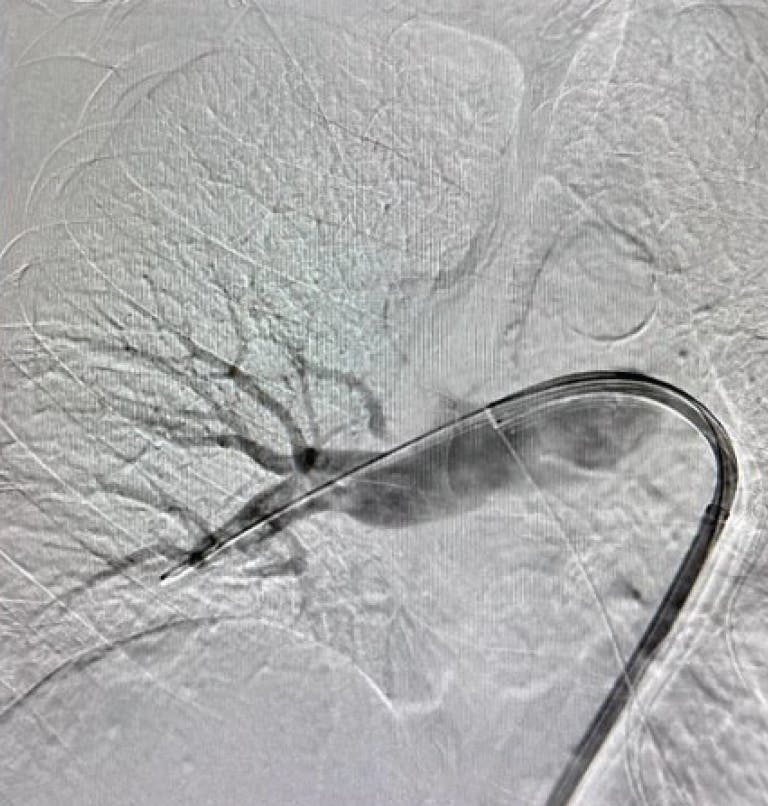

Figure 1. Right lobe initial angiogram.

Figure 2. Left lobe initial angiogram.